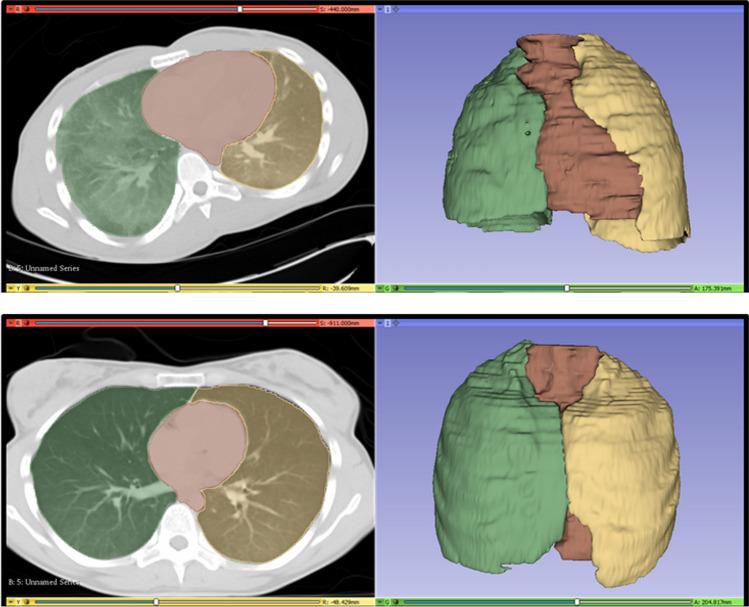

The aim of this study was to measure the mediastinal-thoracic volume ratio (CTR_VOL) on PMCT as a more accurate version of traditional CTR, in order to assess the terminal positional relationship between the heart and lungs in the different causes of death with regard to age, gender, BMI, cardiomegaly, and lung expansion.

Two hundred fifty consecutive postmortem cases with pre-autopsy PMCT and full forensic autopsy were retrospectively evaluated. The lungs and the mediastinum were manually segmented on the PMCT data and the correspondent volumes were estimated in situ. CTR_VOL was calculated as the ratio of the mediastinal to the thoracic volume. The volume measurements were repeated by the same rater for the evaluation of the intrarater reliability. Age, gender, body weight and height, heart weight at autopsy, and cause of death were retrieved from the autopsy reports. Presence of lung expansion was radiologically evaluated in situ.

本研究旨在测量 PMCT 上的纵隔-胸腔体积比(CTR_VOL),作为传统 CTR 的更准确版本,以评估不同死因与年龄、性别、BMI、心脏增大和肺扩张有关的心肺终端位置关系。

回顾性评估了 250 例连续行 PMCT 检查的尸检前病例和完整法医尸检。手动在 PMCT 数据上对肺和纵隔进行分段,并在原位估计相应的体积。CTR_VOL 计算为纵隔与胸腔体积的比值。通过同一评估者重复体积测量,以评估内部评估者的可靠性。从尸检报告中检索年龄、性别、体重和身高、尸检时的心脏重量和死因。在原位通过放射学评估肺扩张的存在。